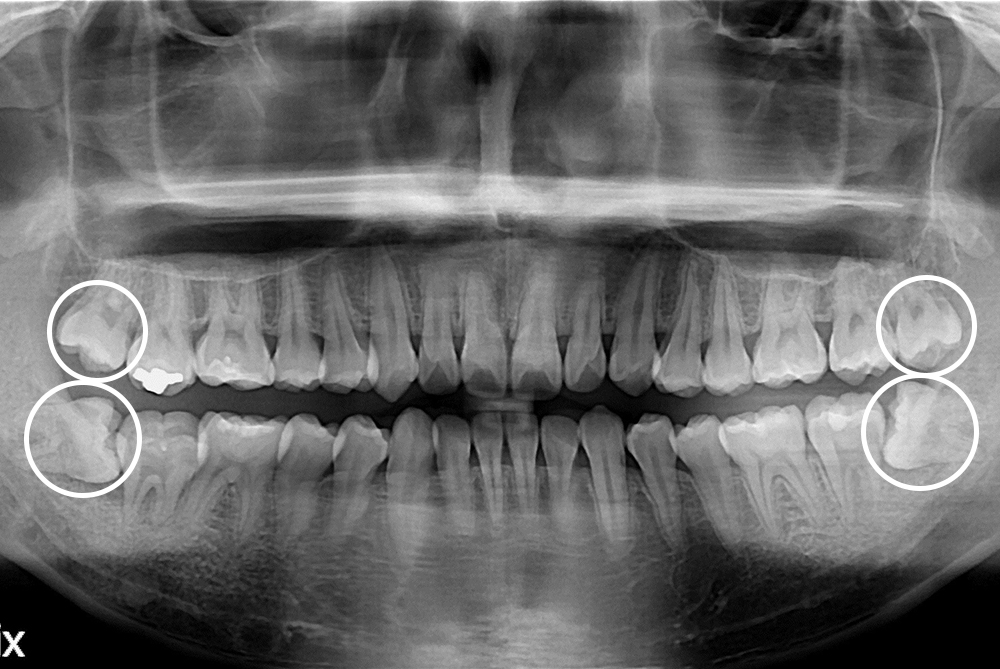

[사랑니] 매복 사랑니 발치

치료전 : 2019-01-02